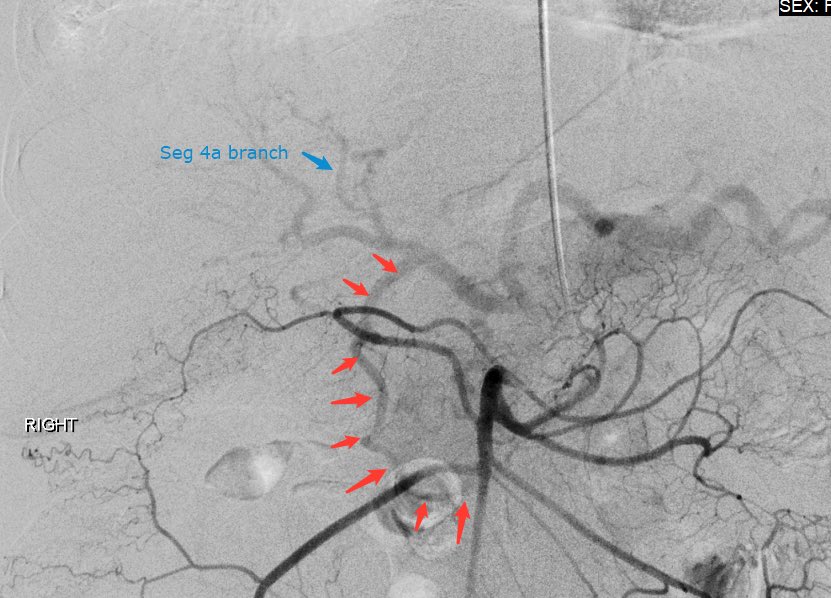

should be an AWESOME outcome #irad

Patient with seg4 HCC and celiac axis atherosclerotic occlusion (and aortioiliac disease). Difficult navigation via SMA collateral to GDA and finally seg4 branch of LHA #Y90. Hoping for a great outcome @MoffittNews @NaineshParikhMD Intra-op CTA @SiemensUSA Maestro @MeritMedical